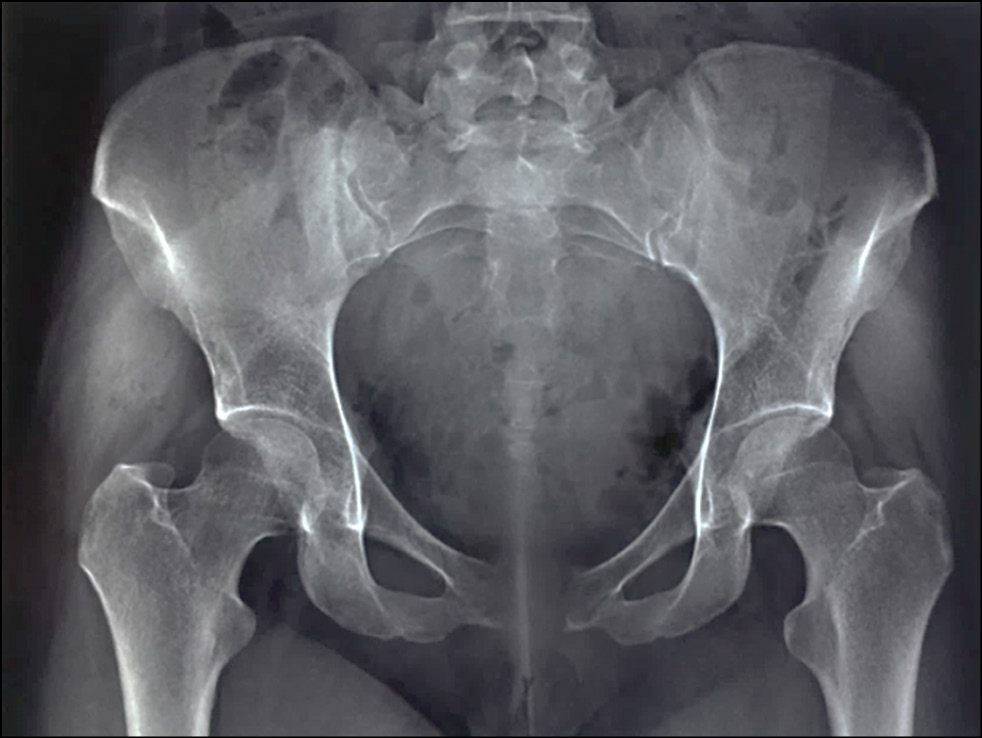

Из анамнеза известно, что боль в области лонного сочленения начала беспокоить в III триместре беременности. После родоразрешения путём кесарева сечения (27.09.2017) боль значительно усилилась, наблюдалось ежедневное повышение температуры тела до 38,8 °C. На рентгенограммах костей таза обнаружено расхождение лонных ветвей до 4 см (рис. 1).

Рис. 1. Обзорная рентгенограмма костей таза пациентки С. Диастаз между лонными костями более 4 см, отмечается нечёткость суставных поверхностей лобковых костей за счёт поверхностных костных эрозий, симметричное распространение процесса на разное расстояние от лобкового симфиза.

Fig. 1. Plain radiograph of the pelvic bones of patient S. Diastasis between the lumbar bones is more than 4 cm, there is a fuzziness of the articular surfaces of the pubic bones due to superficial bone erosion, a symmetrical spread of the process at different distances from the pubic symphysis.